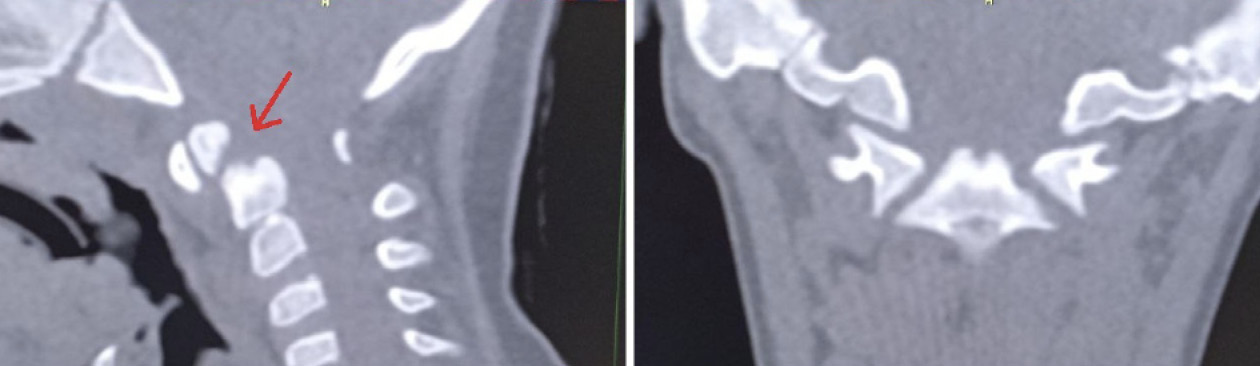

Для оценки ситуации в динамике была проведена КЛКТ, на которой на фоне динамической нерезкости (ребенок был неусидчив) и артефактов от металлоконструкции было отмечено следующее: суставные рентгеновские щели в латеральных атлантоаксиальных суставах: справа – не прослеживается, слева – неравномерно сужена до 0,4 мм в наиболее узком месте (рис. 6). Рентгеновская щель срединного атлантоаксиального сустава в сагиттальной плоскости не прослеживается (рис. 7А), в парасагиттальной плоскости – прослеживается, неравномерная (рис. 7Б). Зубовидный отросток С2 позвонка визуализируется в виде 2 фрагментов, дистальный из которых вместе с передней дужкой С1 позвонка представлен в виде не полностью слитного костного образования. Проксимальный фрагмент, лоцирующийся в проекции верхушки зубовидного отростка С2 позвонка, представлен в виде свободно лежащего отломка с неравномерно склерозированным контуром в проекции диастаза (см. рис. 7). Данная рентгенологическая картина соответствует состоянию после оперативного лечения по поводу травмы шейного отдела позвоночника со стабилизацией металлоостеосинтезом С1–С2 позвонков. Неправильно сросшийся перелом зубовидного отростка С2 позвонка. Частичный анкилоз срединного атлантоаксиального сустава и полный анкилоз правого латерального атлантоаксиального сустава.

Рис. 7. Конусно-лучевая компьютерная томография краниовертебральной области, сагиттальный срез (А), парасагиттальный срез (Б). Стрелкой отмечено место анкилоза срединного атлантоаксиального сустава. Двойной стрелкой обозначен свободно лежащий апикальный костный фрагмент зубовидного отростка аксиса